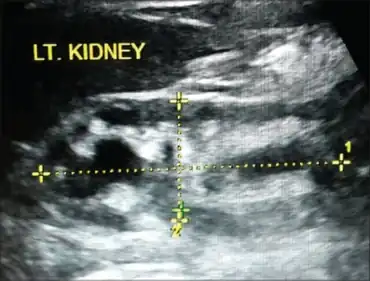

Kidney has moderate hydronephrosis with scarring at lower pole, consistent with reflux nephropathy

It is diagnosed by micturating cystography; scarring can be demonstrated by ultrasound or DMSA.